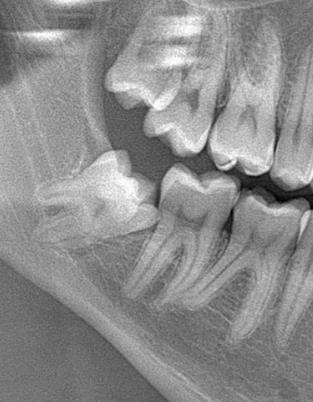

Veja alguns casos de sucesso